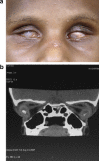

Orbital retinoblastoma is a catastrophic event traditionally carrying a dismal prognosis. Although its incidence is less in the developed countries it continues to be one of the major diagnosis at presentation in the developing world. Orbital retinoblastoma encompasses a wide range of distinct clinical entities with varying tumor load. There are no standard treatment protocols as of now but the current preferred management is multimodal with a combination of initial high-dose chemotherapy, surgery, external beam radiotherapy and prolonged chemotherapy for twelve cycles. In spite of progress on all fronts including surgical, medical, diagnostic, genetic and rehabilitative with improving survival rates, however, lack of access to medical facilities, lack of education about the need for early medical attention and cultural resistance to enucleation continue to contribute to an epidemic of extra ocular disease at diagnosis in the developing world. This review introduces the various terminologies used in the spectrum of orbital retinoblastoma, discusses in details the clinical aspects and management protocols, current status and the future directions.